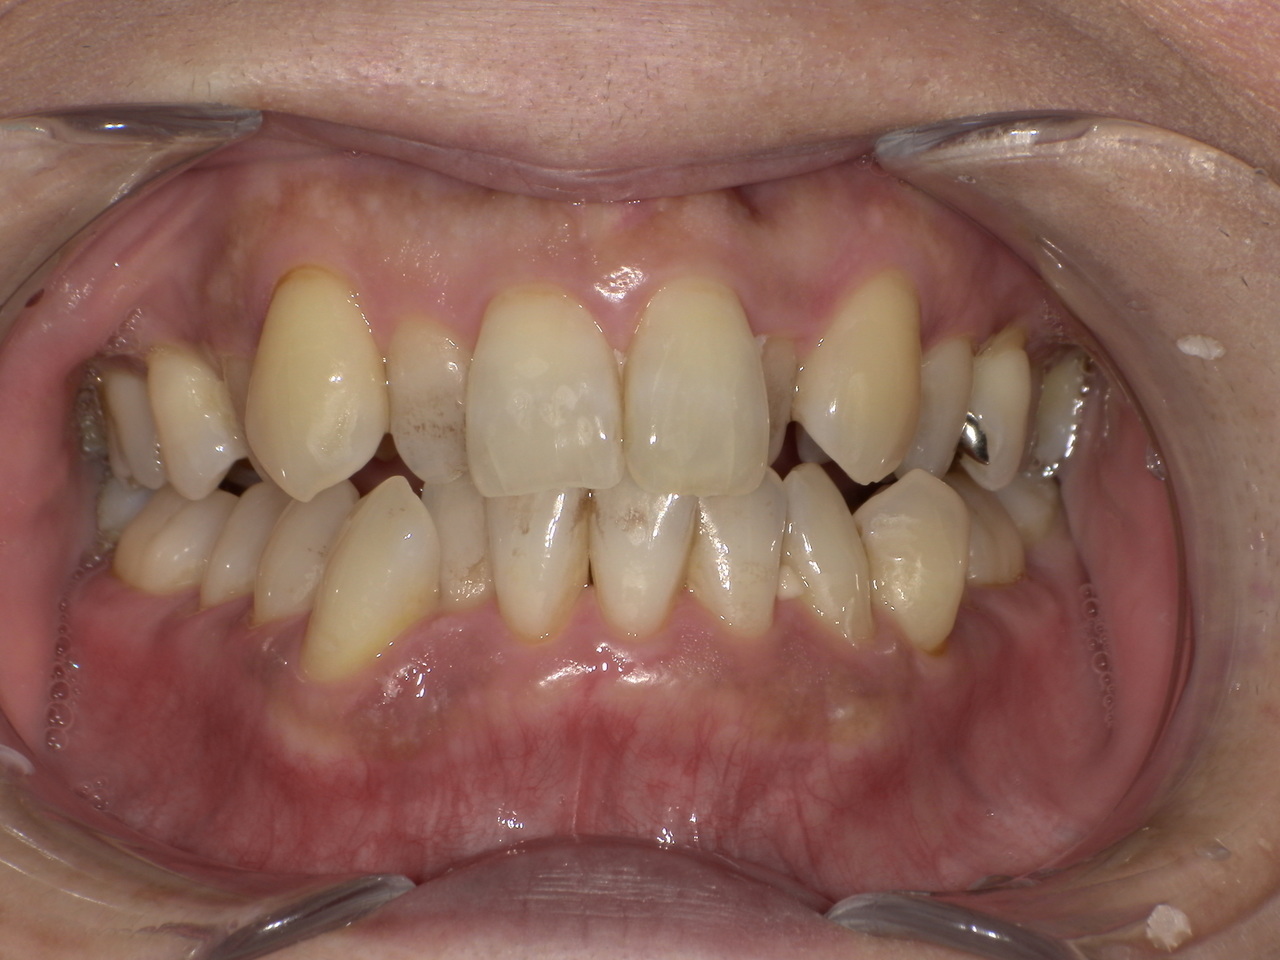

ステイン除去

BEFORE

AFTER

年齢:70代男性

治療内容:エアーフローによる歯の着色汚れ、ステイン除去

治療期間/通院回数:1回

費用: ステインコース 8,800円

リスク・副作用

①効果には個人差があり、着色汚れによっては一度に取りきれない場合があります。

施術後数時間以内に、着色効果の強いもの(コーヒー・紅茶・喫煙など)を摂取すると、歯に色素沈着が起こる可能性があります。

パウダーの刺激により歯ぐきから出血する可能性があります(痛みはほとんどありません)。